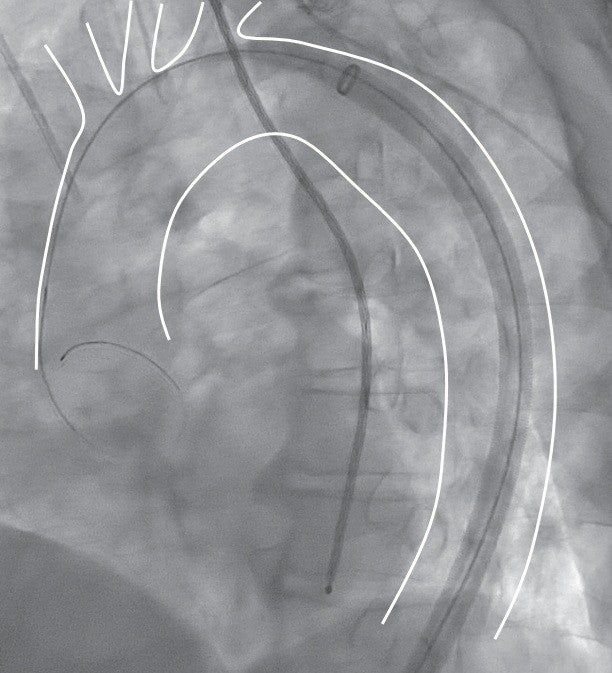

右大腿動脈から6 Frシースを挿入後、上行大動脈までカテーテルを進め、ガイドワイヤーを硬質ガイドワイヤー(EGoist、 Ultimate、 Arch Curve、Medicos Hirata)に交換した。65 cmドライシール フレックス イントロデューサシースをゆっくりと先進させ、大動脈の頂部近くにダイレーターの先端が到達したところまで挙上する(図3a)。

その後にシース外筒のみを約3 cm弱ほど挙上させると大動脈頂部近くまでドライシール フレックス イントロデューサシースが到達する。約3 cmまでであればシース外筒とダイレーターとの段差なく進めることが可能である(図4a, b)。